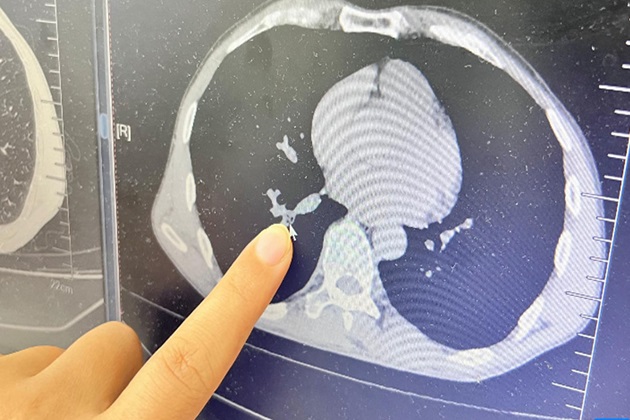

Después de una inspección inicial, el médico especialista en otorrinolaringología Lin Ling determinó que el cuerpo extraño podía estar alojado en sus vías respiratorias inferiores. La exploración del tórax reveló algo raro en su pulmón derecho. Al día siguiente, el paciente fue sometido al procedimiento quirúrgico bajo anestesia local y el equipo médico pudo identificar y extraer la cucaracha envuelta en abundante flema.